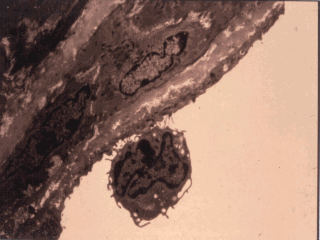

What might acute phase cytokines do? This slide shows an

effect of cytokine activation of endothelial cells. These cells on stimulation with TNF-alpha,

IL-1, IL-6 expressed number of adhesion molecules causing rolling and the adherence of

lymphocytes which may will be the earliest phases of the formation of fatty streaks in the

atherosclerotic plague. |